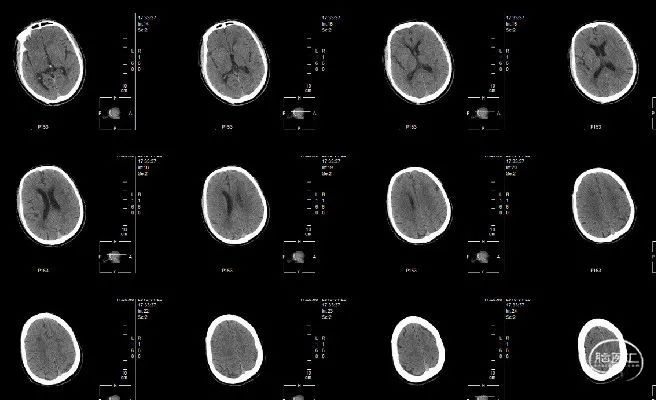

现病史:缘于入院5小时前(2018年4月23日12时10分)无明显诱因突发右侧肢体无力,右侧肢体完全不能动弹,伴口角歪斜,伴对答不能、理解障碍,无呕吐,无大小便失禁、人事不清,无吞咽困难、饮水呛咳、呼吸困难,急诊我院,行头颅CT未见新鲜梗塞灶及出血灶,未见致密征,发病前mRS 0分,发病后mRS 4分,ASPECTS评分10分,急诊拟“急性脑梗塞”收住院。本次患病以来,精神尚可,未进食及睡眠,大便未解,小便正常。

查体情况:NIHSS 16分;ASPECT评分10分。

右侧股动脉穿刺,穿刺至发病时间8小时。行全脑血管造影示:患者左侧颈内动脉闭塞(ICA),闭塞血管直径约3.1mm,TICI 0分,前交通、后交通均开放,右侧颈内动脉通过前交通代偿左侧大脑中动脉及左侧大脑前动脉供血区,左侧后交通开放,并左侧颈内动脉末端逆行显影,左侧大脑后动脉通过脑膜支部分代偿左侧大脑中动脉供血区。

术前对侧循环造影可见前交通动脉开放,左侧M1段有狭窄。

行椎动脉造影,可见后循环开放,血液可通过后交通动脉向大脑中动脉代偿。

术后30小时随访:NIHSS评分0分,CT未见出血、大面积脑梗等情况。

术后7天随访:NIHSS评分0分。